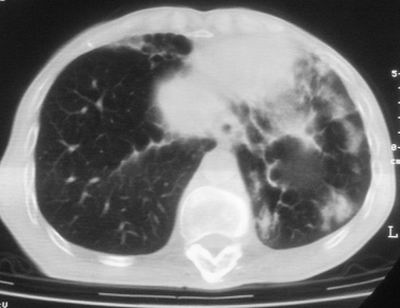

标题: CT11864:男,47岁,反复咳嗽、咯痰、咯血3年,请分析. [打印本页]

患者,男,47岁,反复咳嗽、咯痰、咯血3年,再发5天。痰培养未找到真菌、抗酸杆菌、癌细胞。

左肺上叶体积明显缩小,其内见多发透光区,纵隔向左侧移位,左肺下叶多发班片状病灶,边界模糊,1左肺上叶先天肺发育不全,2左肺下叶肺炎,

左肺上叶结核伴肺纤维化,纵隔移位,左肺下叶感染性病变,建议抗炎抗结核后复查,双肺气肿.

以下是引用xulianj在2008-2-25 21:01:00的发言:[br]左肺上叶结核伴肺纤维化有霉菌球形成,纵隔移位,左肺下叶感染性病变,建议抗炎抗结核后复查,双肺气肿.

考虑:左肺慢纤伴霉菌球形成、双肺全小叶型肺气肿。

1)考虑为:左肺上叶肺结核(空洞形成),伴左下肺感染;不排除霉菌感染可能。2)肺气肿。

左肺上叶结核伴肺纤维化空洞形成并左肺下叶感染,纵隔牵拉移位,建议作进一步检查排除左侧肺霉菌感染可能。